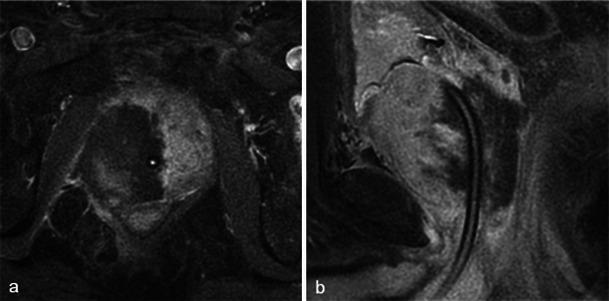

In this technique, a photosensitising agent is introduced intravenously, then activated by local laser illumination to induce tumour necrosis. Treatment efficacy is assessed by magnetic resonance imaging (MRI).

We illustrate specific post-treatment MRI aspects at early and late follow-up with pathological correlations.

• Dynamic phototherapy is a new and promising focal therapy for prostate cancer. • One-week MRI shows increased volume of the treated lobe and large, homogeneous necrosis area. • Six-month MRI shows significant changes of the prostate shape and signal. • Six-month MRI becomes "base line" appearance for further follow-up or monitoring.

在该技术中,将一种光敏剂静脉注射,然后通过局部激光照射激活以诱导肿瘤坏死。通过磁共振成像(MRI)评估治疗效果。

我们阐述了早期和晚期随访时特定的治疗后MRI表现及其与病理的相关性。

• 动态光动力疗法是一种用于前列腺癌的新型且有前景的局部治疗方法。• 一周后的MRI显示治疗叶体积增大以及大片均匀的坏死区域。• 六个月后的MRI显示前列腺形态和信号有显著变化。• 六个月后的MRI成为进一步随访或监测的“基线”表现。